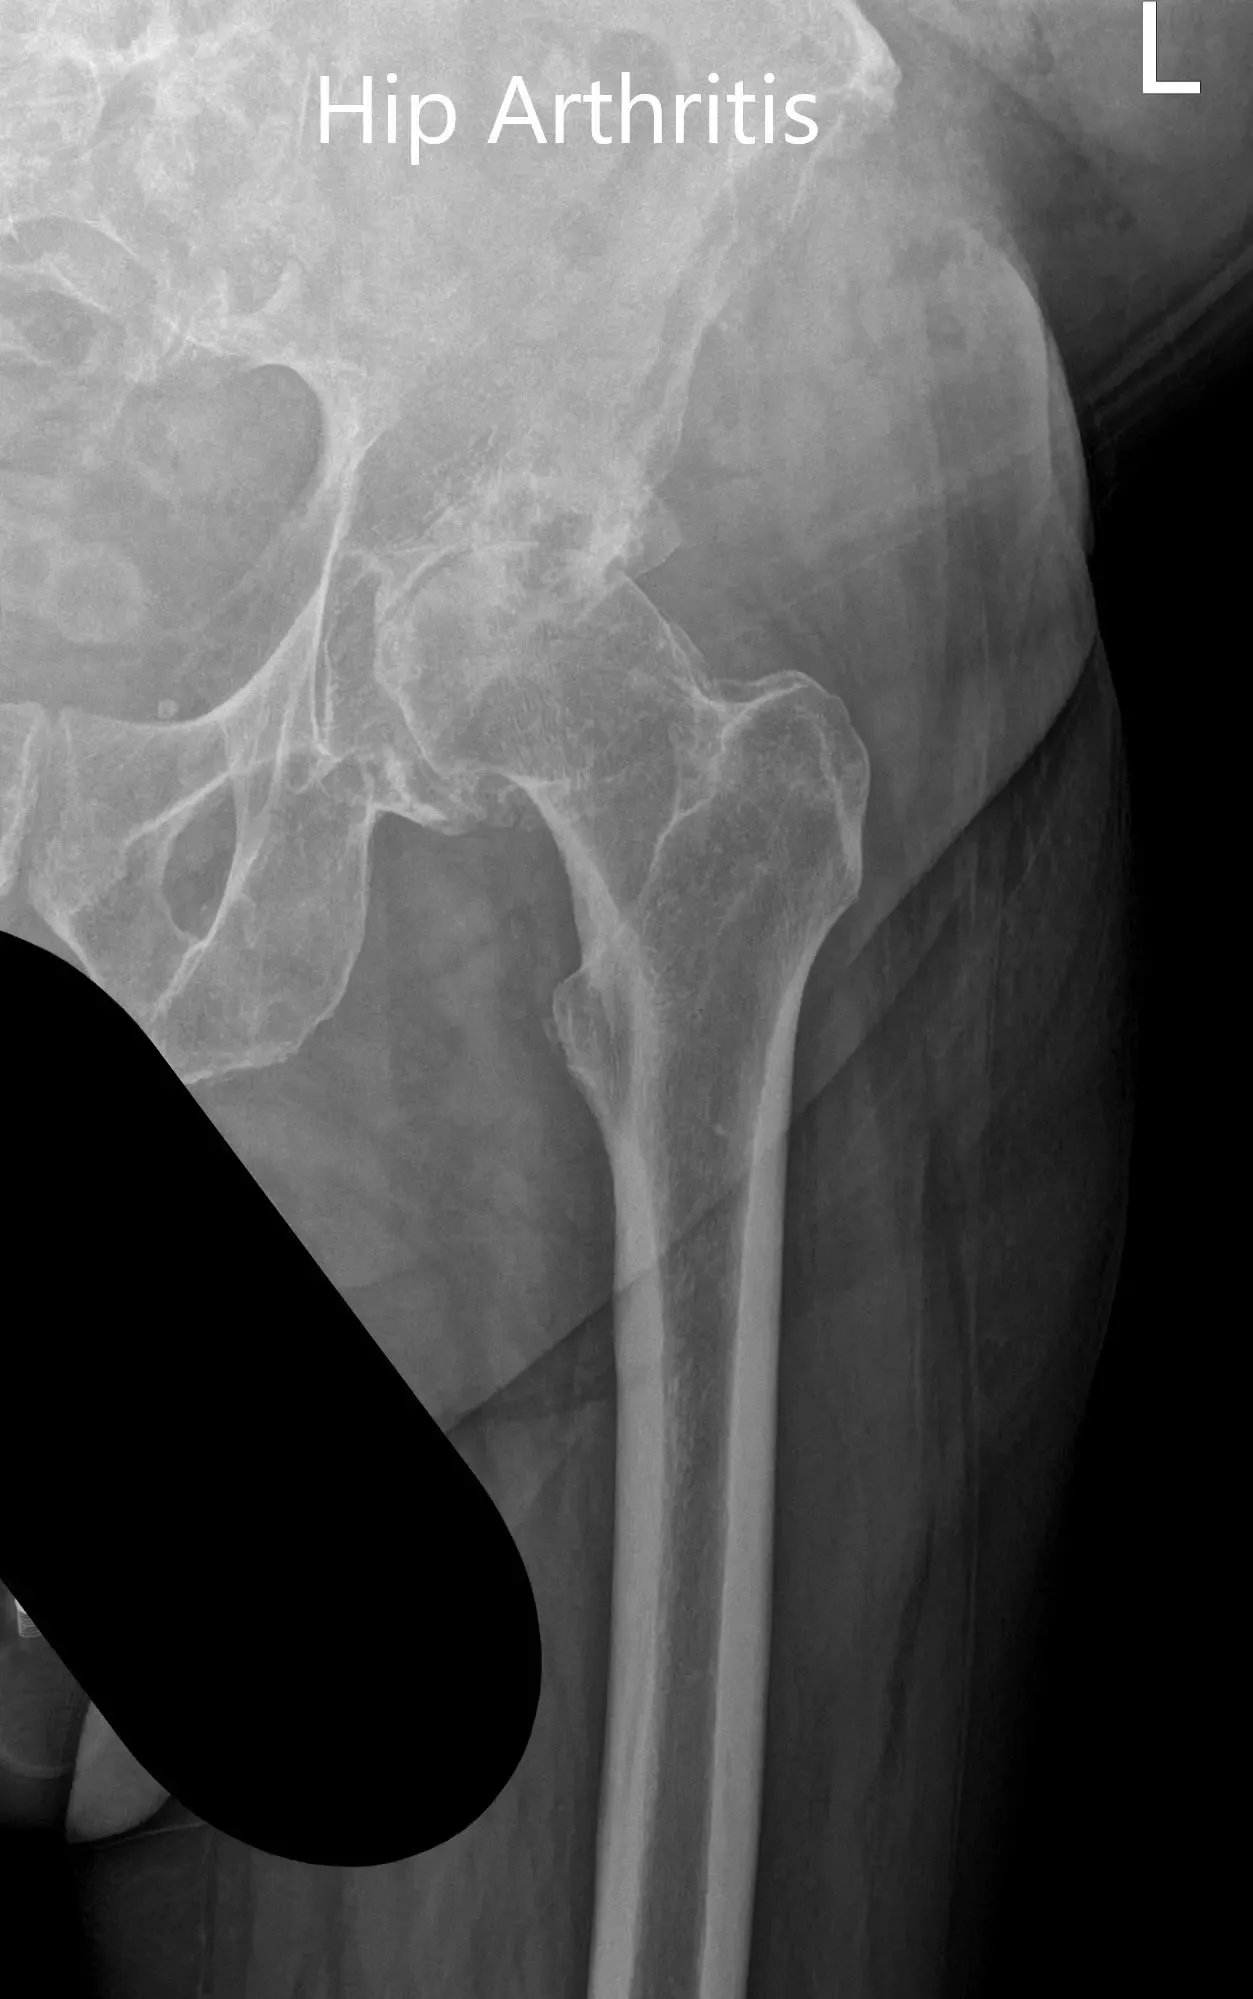

Las imágenes revelaron cambios osteoartríticos en la articulación izquierda de la cadera con reducción del espacio articular, quiste subcondral, esclerosis y osteófito. Tras agotar las opciones de manejo conservador, se recomendó al paciente una prótesis total de cadera. Se discutieron extensamente con el paciente los riesgos, beneficios y alternativas. Ella aceptó seguir adelante con el procedimiento.

Radiografía preoperatoria que muestra la vista Judet de la pelvis.

Radiografía preoperatoria que muestra la vista lateral en forma de rana y la vista en ángulo de la cadera izquierda.